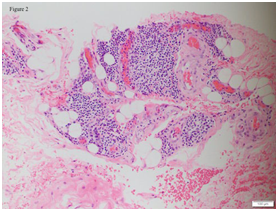

Patient was co-managed with the department of haematology and oncology to rule out systemic involvement. Further biopsies were conducted and they took samples from his cervical lymph nodes and bone marrow. His lymph nodes had evidence of marginal zone B-cell lymphoma and suggestion of secondary nodal involvement of an extra-nodal mucosa-associated lymphoid tissue (MALT) lymphoma (Figure 3 and 4; lymph node histology). His right posterior superior iliac spine bone marrow biopsy was also consistent with B-cell lymphoma infiltrate. There were generalized lymphadenopathy from skull base to inguinal region together with bilateral renal hilar soft tissue infiltration noted on computed tomography of his chest, abdomen and pelvis consistent with the diagnosis of Non-Hodgkin lymphoma. An upper gastrointestinal tract endoscopy was also performed and revealed no gastrointestinal involvement.

Figure 3 Lymph node biopsy: High magnification image highlighting effaced nodal architecture. The predominant small ‘B’ lymphoid cells show monocytoid, centrocyte-like and few plasma cells (Hematoxylin and Eosin, 100X).